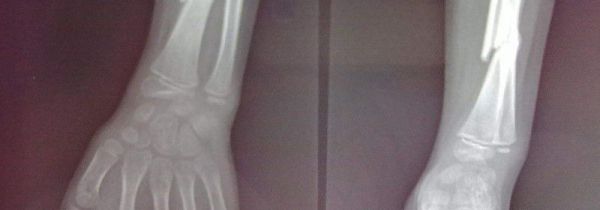

尺骨和桡骨的正确位置

尺骨和桡骨都是人体上肢前臂的骨头,尺骨的位置在胳膊内侧,前臂两根长骨之一中较长的骨头就是尺骨。而桡骨的位置在上…